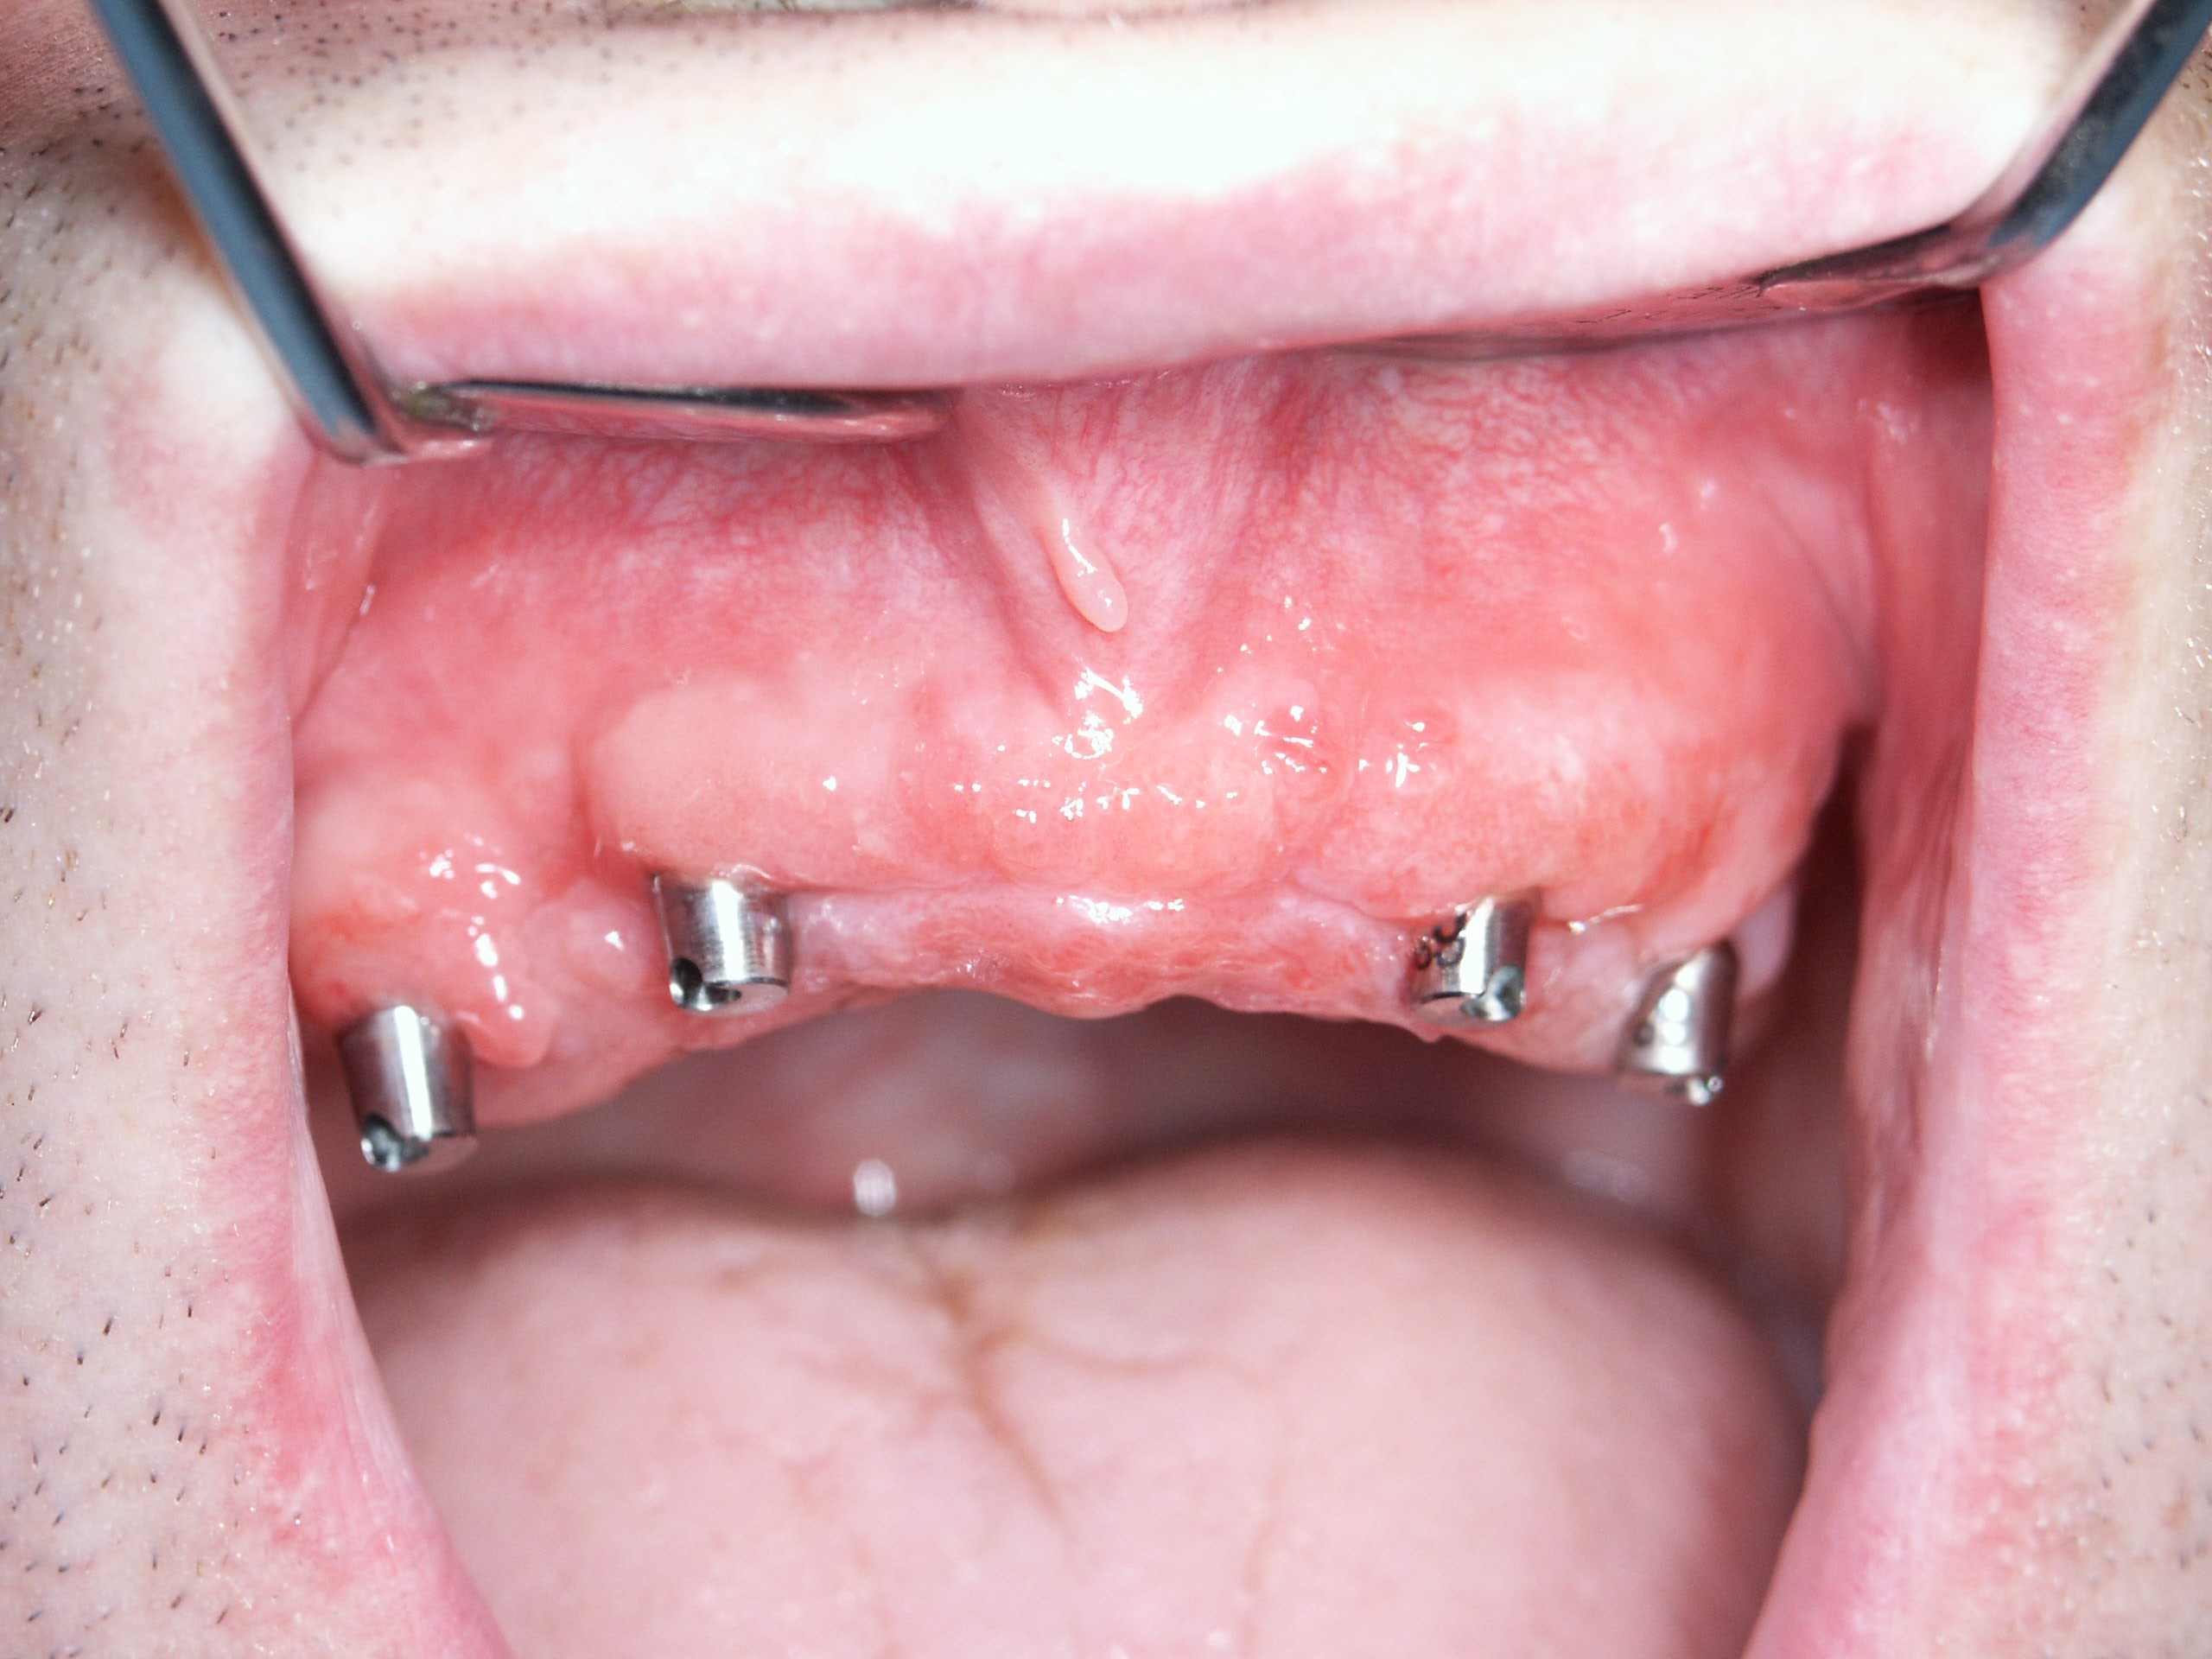

i quattro impianti con i rispettivi monconi e la sutura

la protesi inserita e caricata immediatamente